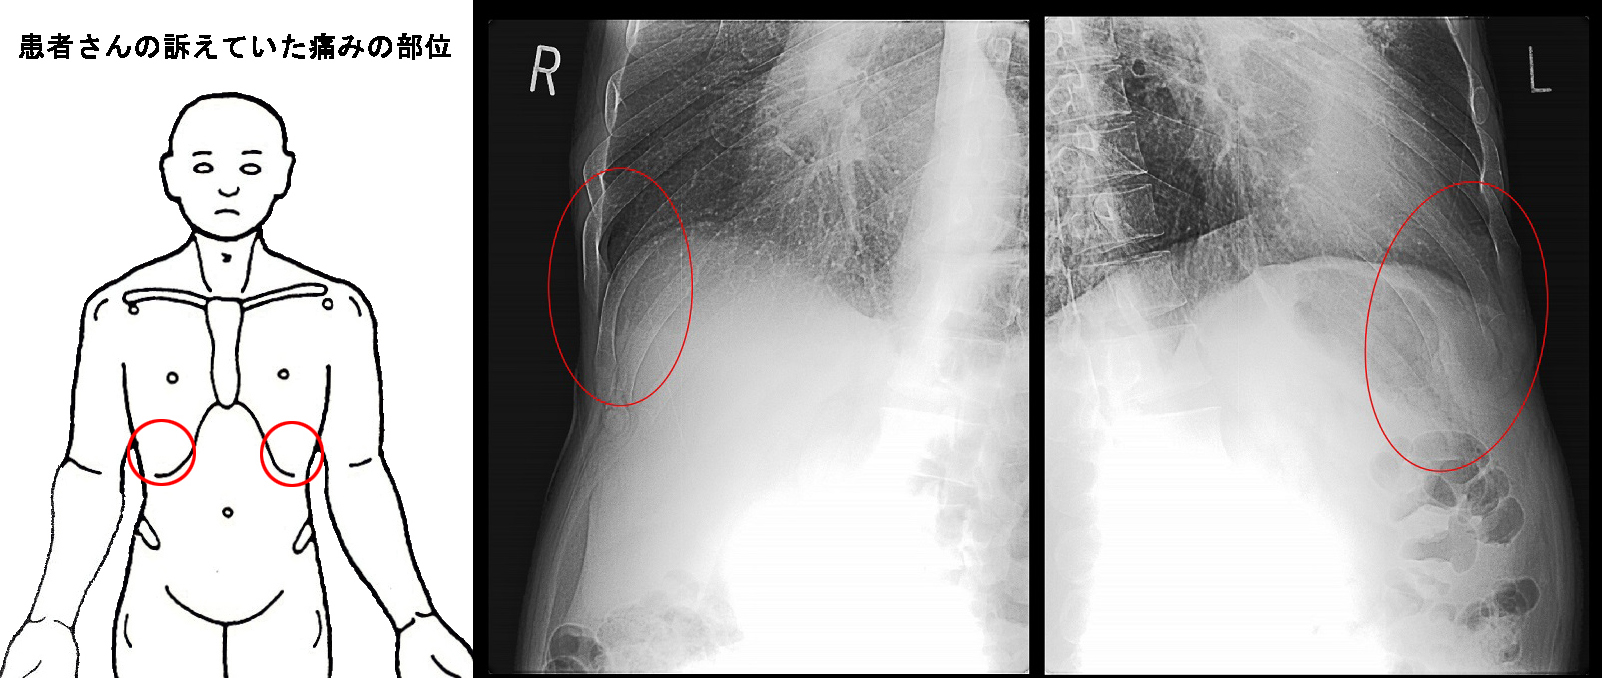

患者さんは両側の前胸部に尋常でない痛みがあると訴えていましたが、

除染作業員・初診・疲労骨折部位2.jpg

その病因は背側の両側肋骨の疲労骨折でした。疲労骨折は右下MRI画像の赤矢印部分です。

青丸が患者さんが痛みを訴えていた部位となります。